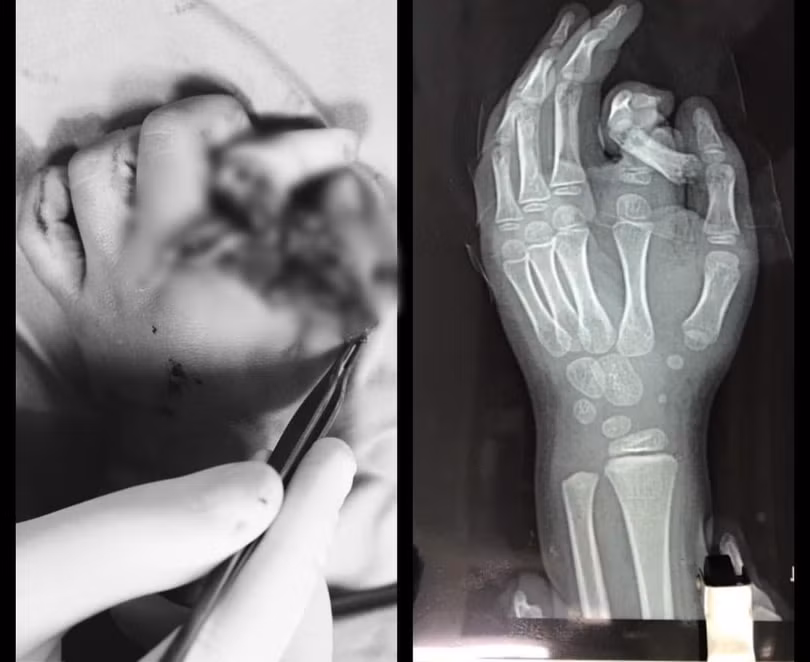

Bé N.T.T., 6 tuổi, sống ở Hà Nội vào Khoa phẫu thuật tạo hình và thẩm mỹ, Bệnh viện Đa khoa Xanh Pôn trong tình trạng ngón trỏ bị đứt rời, xoắn vặn, hệ thống thần kinh dây chằng bị nhổ bật một đoạn dài, chỉ vì cháu cho tay vào máy giặt đang hoạt động.

Ngay khi tiếp nhận bệnh nhi, các bác sĩ đã cố gắng bảo tồn ngón tay bị đứt rời để nối lại cho bé. Tuy nhiên, do ngón tay trỏ bị dập nát quá nặng và bé còn nhỏ nên việc nối ngón tay chưa thế thực hiện được.

| Bác sĩ khám ngón tay cho bé trai ở Bệnh viện Đa khoa Xanh Pôn (Ảnh: BVCC) |